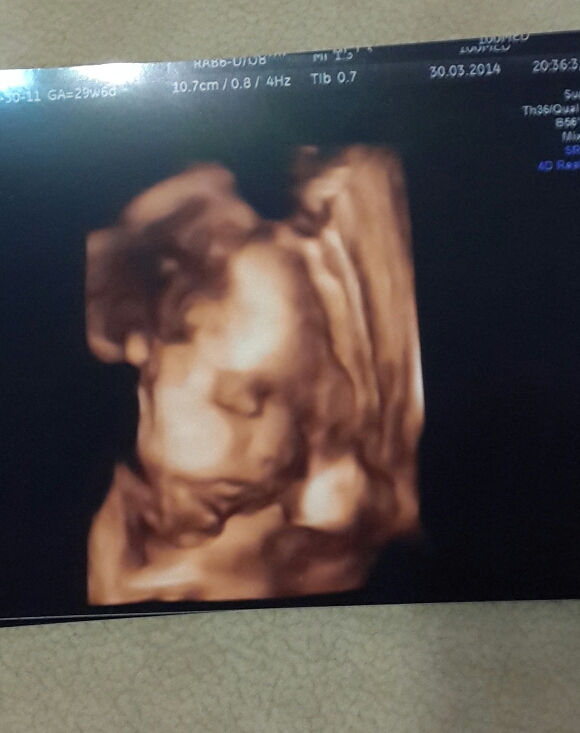

Фото пузиковнам 30 неделек ( завтра)))) раньше казалось 30 ого как много)))Всё у нас в норме, и в4с и состояние хорошое, бвла сегодня на узи, весим в 29.6 1400 , а по замерам мы ровно на неделю отстаем, видела свою крошечку, зевала, палец сосала и даж глазки открывала, так здорово, целый час смотрела любовалась потом она отвернулась)))) вод немного меньше чем положено, но не критично, через 2 недели опять на узи , спросила про болючие шевеления сказала что малышка крупная и из за небольшого маловодия. а так все хорошо,;живот у меня заметно подрос за неделю, но все равно как то его ощущаю , не мешает вообще, а еще Марго очень пасивная, интересно родится такая же будет, последнии шевеления перед сном в 10-11, спит всё ночь и просыпается утром после 9))) вот как то так фотоотчёт под катом фото 29 и 30 недель и щекастая Маргаритка